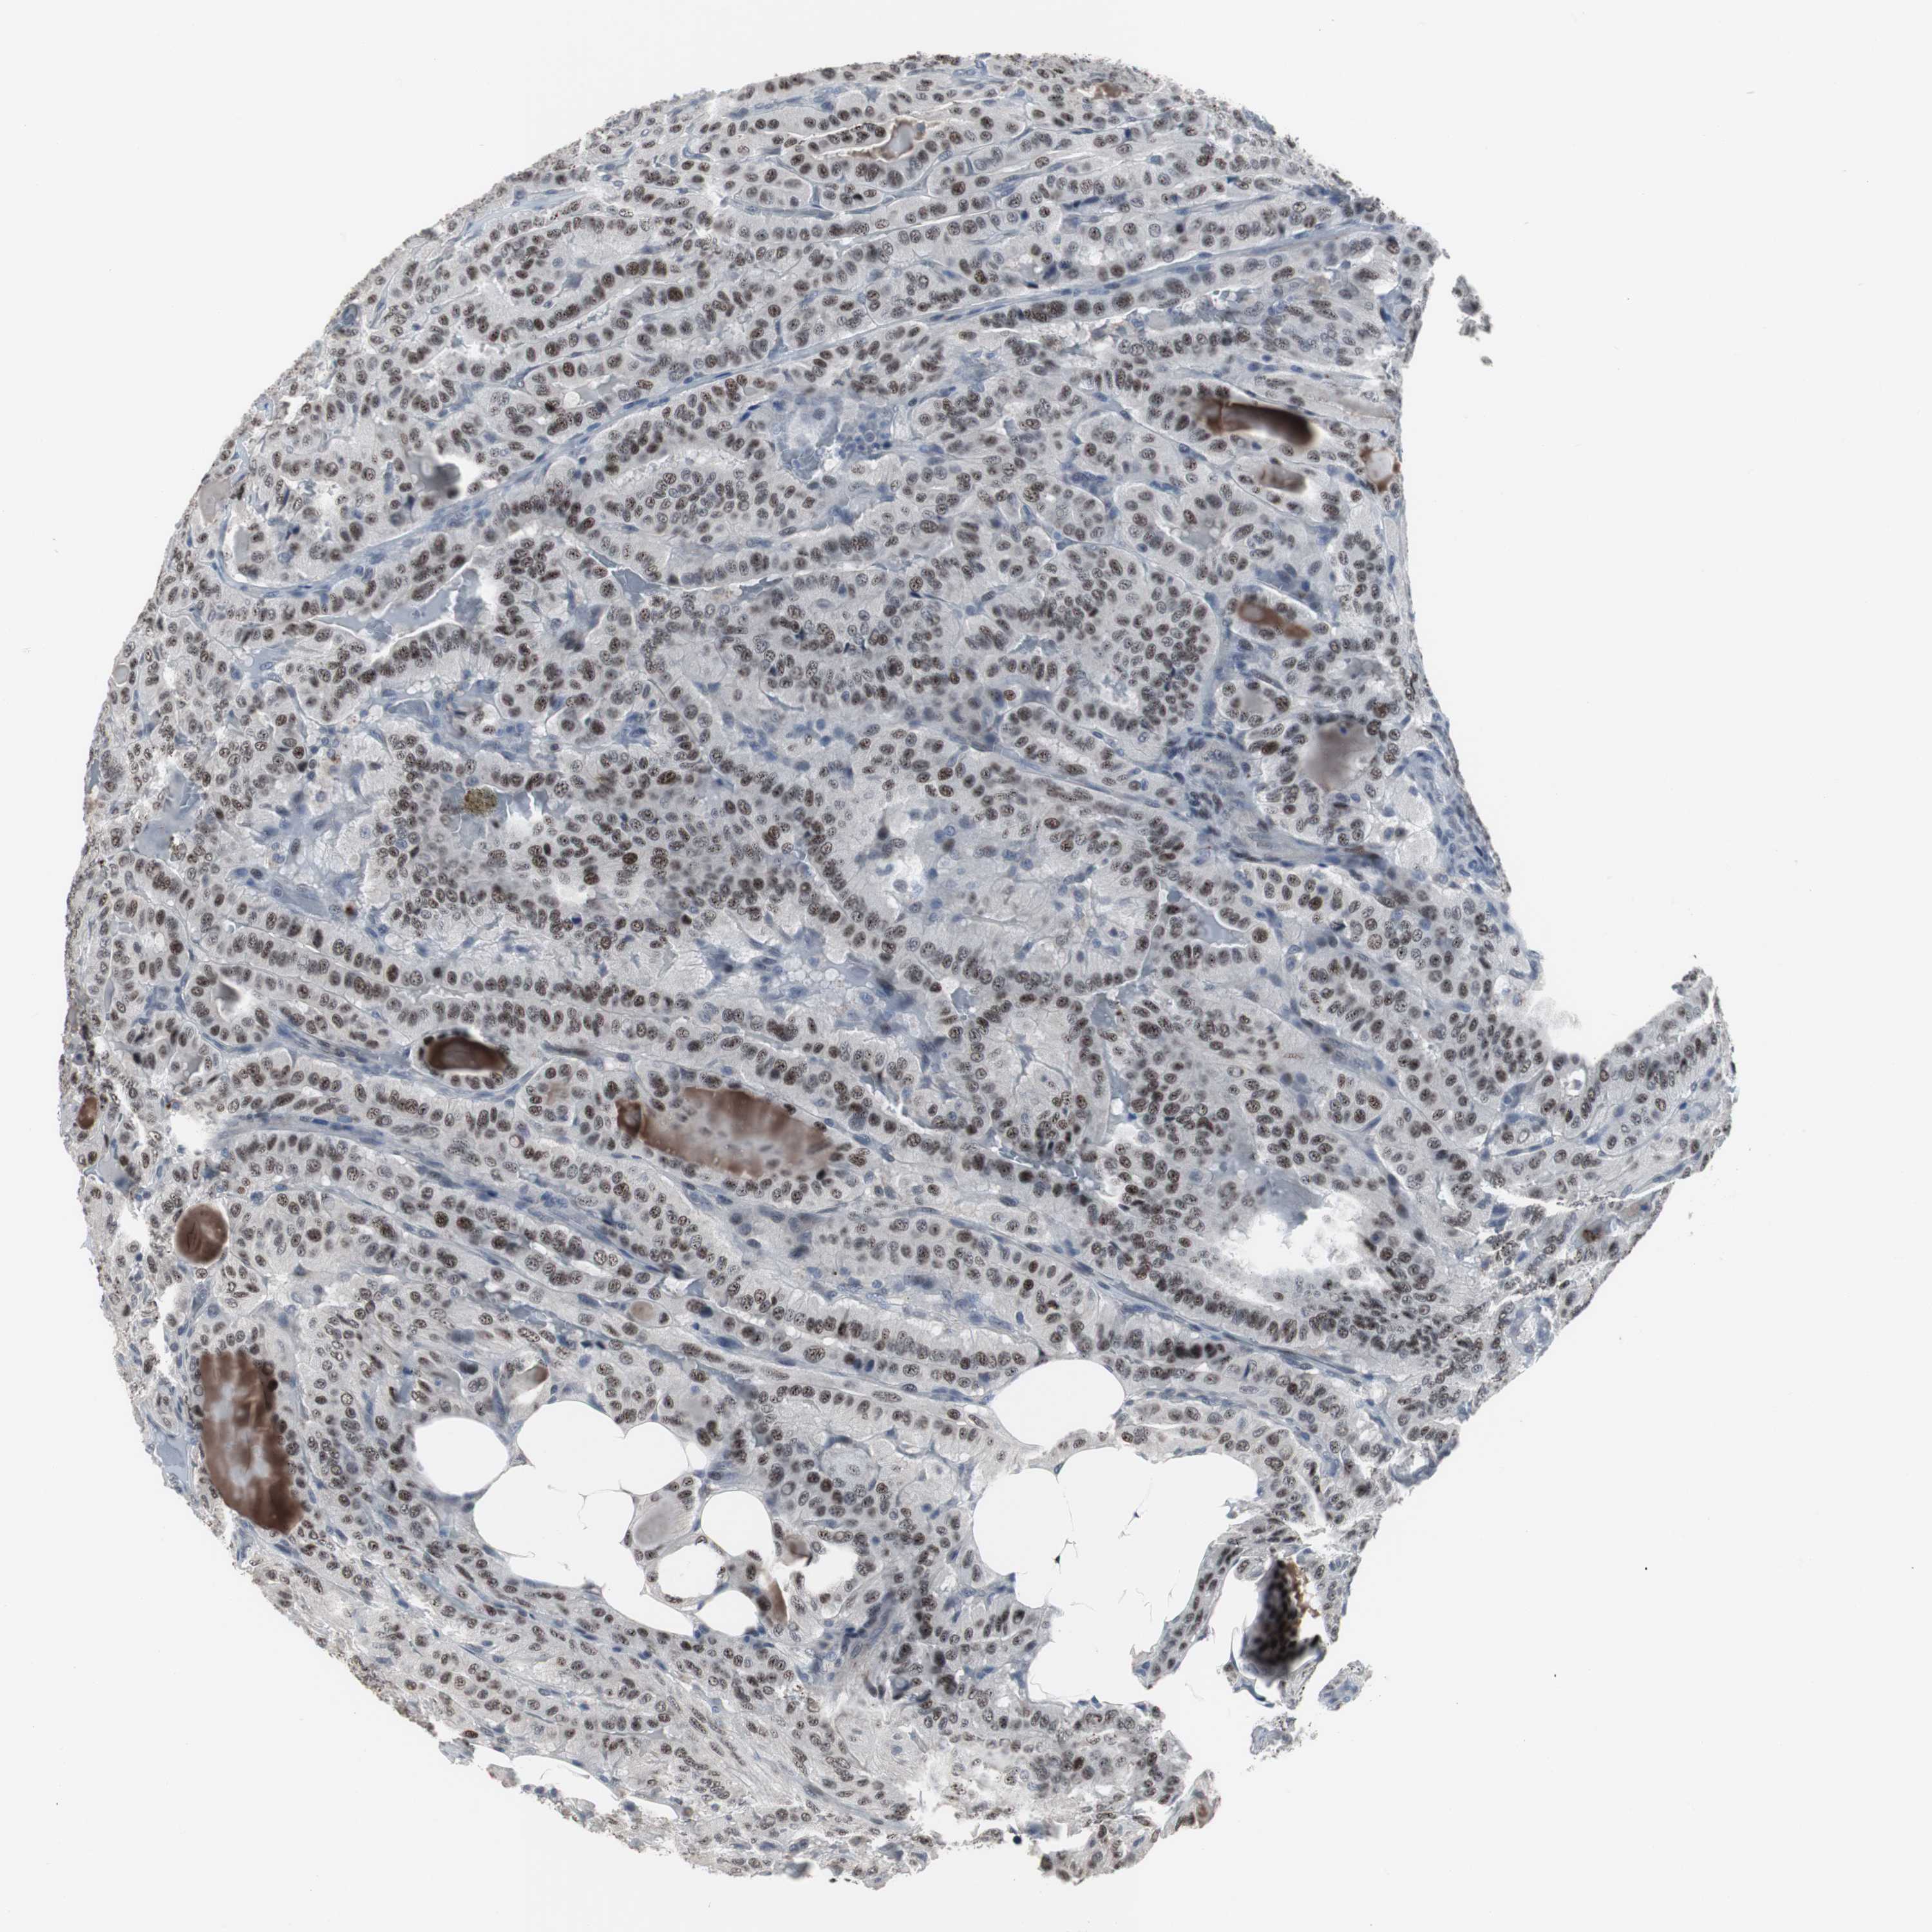

THYROID CANCER - Protein expressioni

A mouse-over function shows sample information and annotation data. Click on an image to view it in a full screen mode. Samples can be filtered based on level of antibody staining by selecting one or several of the following categories: high, medium, low and not detected. The assay and annotation is described here.

Note that samples used for immunohistochemistry by the Human Protein Atlas do not correspond to samples in the TCGA dataset.

Antibody stainingi

Antibody staining in the annotated cell types in the current human tissue is reported as not detected, low, medium, or high, based on conventional immunohistochemistry profiling in selected tissues. This score is based on the combination of the staining intensity and fraction of stained cells.

Each image is clickable and will lead to virtual microscopy that enables deeper exploration of all samples and also displays staining intensity scores, fraction scores and subcellular localization as well as patient and tissue information for each sample.

Antibody HPA007176

Staining

High

Medium

Low

Not detected

Intensity

Strong

Moderate

Weak

Negative

Quantity

>75%

75%-25%

<25%

None

Location

Nuclear

Cytoplasmic/membranous

Cytoplasmic/membranous,nuclear

Papillary adenocarcinoma, NOS

Follicular adenoma carcinoma, NOS